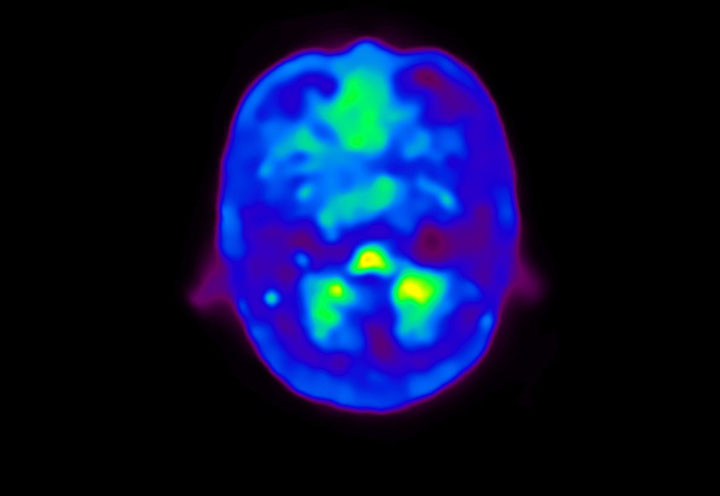

Head / Case4 : Amyloid

Coronal

Courtesy : Kindai University Hospital

- Imaging protocol

- Injected dose: 3.21 MBq/kg, 18F-Flutemetamol

- Uptake time: 100 minutes

- Scan time: 20 minutes